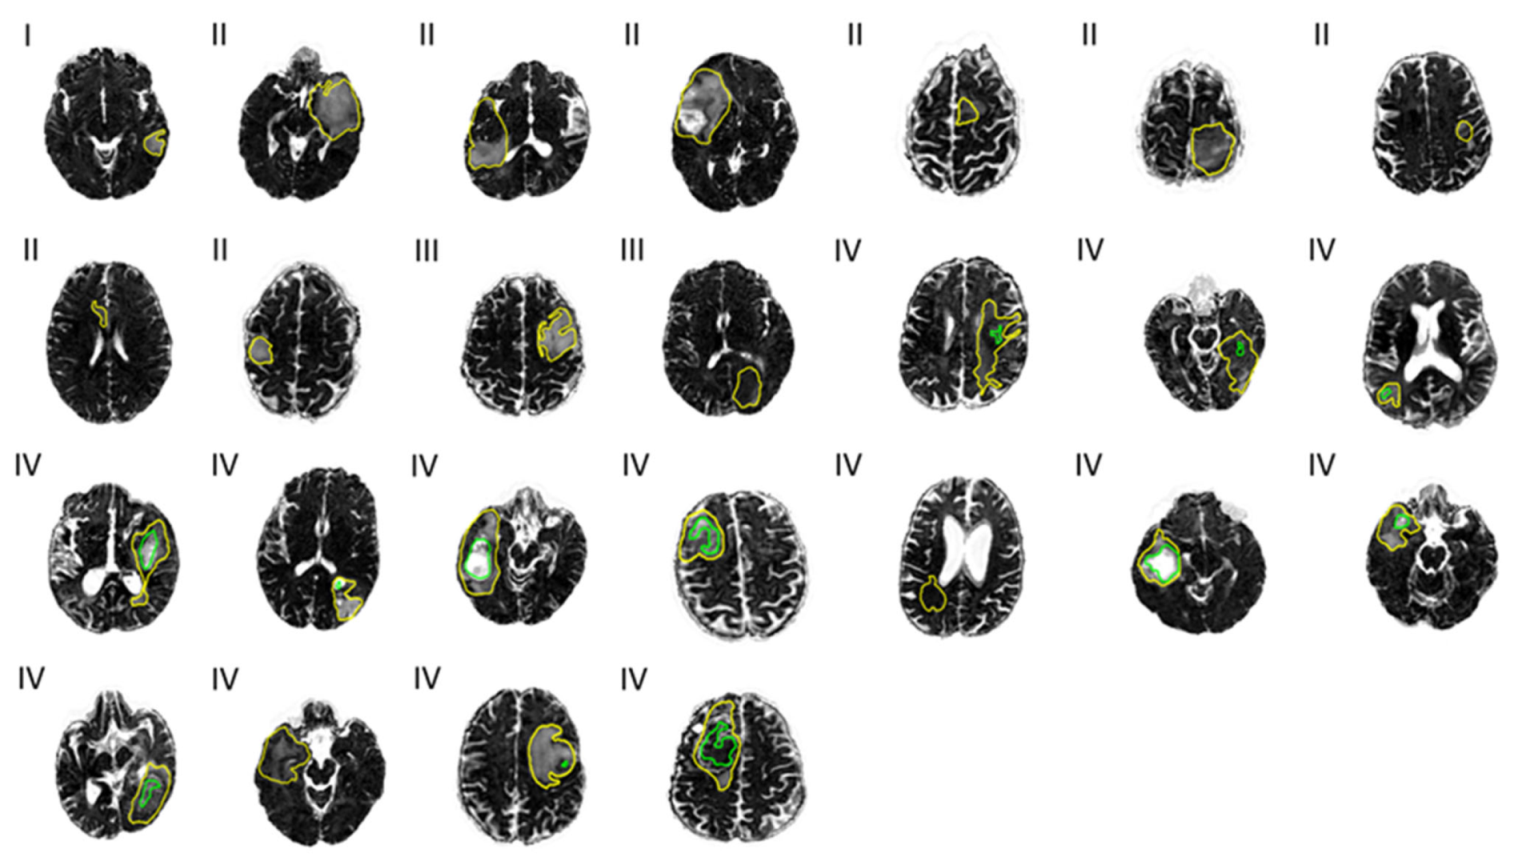

ROC curves were calculated based on voxel-wise labelling of necrotic and enhancing tumor regions and a logistic regression model and show that necrotic tumor regions can be better differentiated using FW-corrected data than with regular FA maps. Results are shown from a single patient in Figure 4. In this patient, the average area under the curve (AUC) is greater than average. Across all patients, the AUC was 0.77 based on FAt, 0.73 with FA, and 0.77 with FW. Enhancing tumor regions were defined as the true positive and the adjacent necrotic tumor regions as the true negative. When enhancing tumor regions are separated from the adjacent non-enhancing tumor regions and non-enhancing tumor regions are labelled as the true positive, the AUCs are 0.66, 0.67, and 0.62 in FAt, FA, and FW, respectively.

Figure 4. Receiver operator characteristics (ROCs) based on voxel-wise labelling. (a) ROC curves separating necrotic and enhancing tumor regions, and (b) ROC curves separating enhancing and non-enhancing tumor regions. Enhancing tumor region is defined as the true positive and the adjacent necrotic tumor region as the true negative. The patient is the same as the one shown in all single patient examples in this paper. The data were fitted to a logistic regression model and the ROC was computed for free-water (FW)-corrected fractional anisotropy (FA) (blue), non-corrected FA (red), and FW (green). Area under curve (AUC) is rendered in corresponding colors.